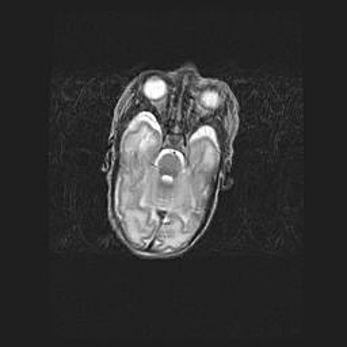

Мальформация Денди-Уокера. Киста задней черепной ямки.

Агенезия мозолистого тела.

Возраст: 2,5 месяца

Вес: 2420 г

Пол: женский

Окружность головы: 37 см

Срок гестации: 32 недели

Мальформация Денди—Уокера — редкий вид патологии ЦНС, представляющий собой врожденный порок развития каудального отдела ствола и червя мозжечка, ведущий к неполному раскрытию срединной (Мажанди) и латеральных (Лушка) апертур IV желудочка мозга. Для этогно синдрома характерна триада симптомов: гипотрофия червя мозжечка и/или полушарий мозжечка, кисты задней черепной ямки, гидроцефалия различной степени. В 70% случаев порок сочетается и с другими аномалиями головного мозга, в частности с агенезией мозолистого тела.